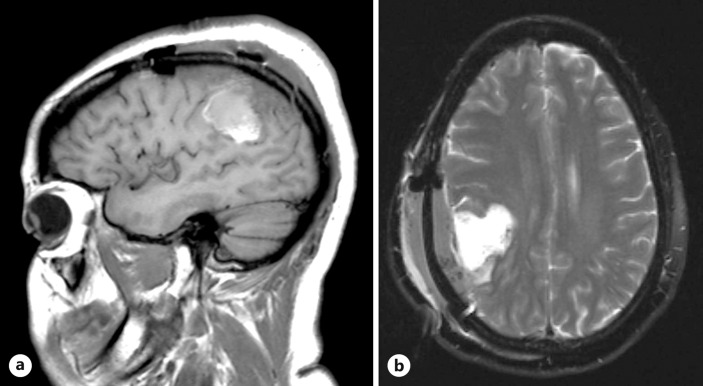

Case presentation: The current article describes the case of a 40-year-old G3P1101 female at 10 weeks' gestation, who sought medical care for recurrent left hemifacial twitching, eventually leading to nonconvulsive status epilepticus. Intubation and sedation were required to achieve seizure cessation. Imaging revealed a lobulated cystic mass in the right parietal lobe, suspicious for low-grade glioma. Despite thorough explanation of the potential risks, the patient adamantly wished to pursue surgical intervention. An uneventful craniotomy was performed for resection of a low-grade glioma. No patient or fetal complications were encountered, and the patient has not had any reported seizures since surgery.